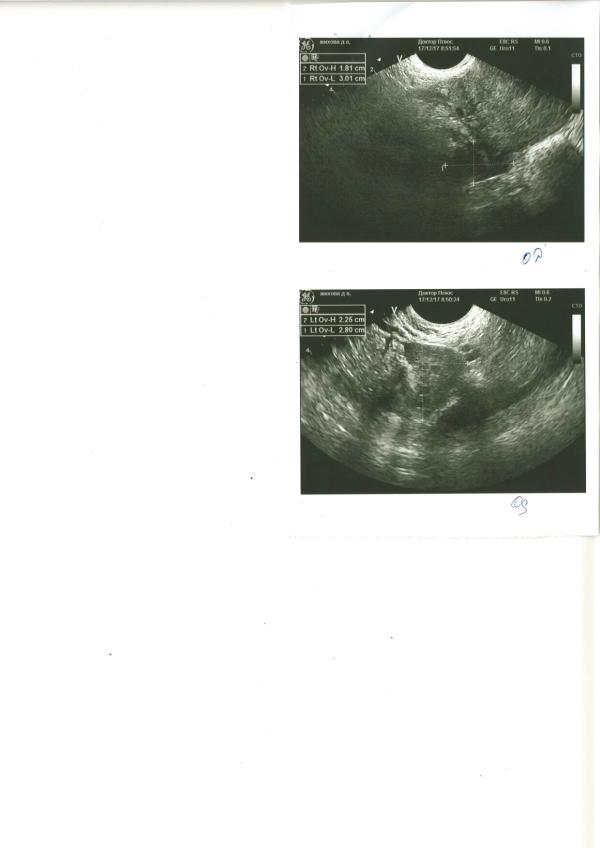

Не выдержала, сходила на УЗИ. Плодное яйцо - 3,6 мм, полость матки расширена до 1,5 мм, анэхогенное содержимое. Полагаю что это содержимое и есть та сама кровь, которая выделялась при походе по "большим делам". Сейчас никаких выделений нет, пью дюф по 2 таблетки в день, живот изредка прихватывает. Планирую попасть к гинекологу сегодня без записи. Волнует вопрос - кто с таким сталкивался и чем это грозит?

У меня в 5 недель тянуло живот и болела поясница,пошла на узи-там отслойка 1.5 см на 3 мм,неделю пила лекарства, через 5 дней отслойки не было, осталась гематома(кровь в полости матки,как у Вас).Пью дюфастон,валерьянку и витамины,сказали не страшно,рассосется,ну и малыш растет,сердечко бьётся.Главное половой и физический покой,побольше отдыхайте и не нервничайте,всё будет хорошо)

Ну это образование и есть гематома. Покой половой и физический , нестрогий постельный режим. Не пугаться, если увидите выделения , гематома опорожняется. Ну и к врачу конечно. Но лечения для гематомы нет, к сожалению. Можно попробовать выяснить причины появления , как частый вариант - прогестероновая недостаточность. Но там ещё с десяток причин может иметь место быть.